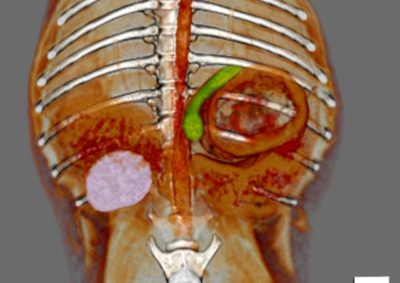

軟部組織外科 注意 ボタンをクリックした先に、治療中および手術中の画像が説明で使用されている場合がございます。 そのような画像に弱い方は閲覧なさらないようお願いいたします。 軟部組織外科 異物による唾液腺の穿孔 軟部組織外科 犬の尿管結石に対する結石摘除 救急・集中治療軟部組織外科 猫の尿管結石に対する尿管切除吻合術#11 軟部組織外科 PSS 犬の門脈体循環シャント 軟部組織外科 猫のPSS 軟部組織外科救急・集中治療 胆嚢摘出 軟部組織外科 予防的胃固定術 Lap−Gastropexy 軟部組織外科 特発性出血性心タンポナーゼ 軟部組織外科 猫の腎膿瘍 軟部組織外科 犬の特発性乳び胸 軟部組織外科 短頭種気道症候群 軟部組織外科 犬の腟脱 <«789101112131415> 症例カテゴリー 放射線治療整形外科軟部組織外科脳神経外科内科腫瘍外科救急・集中治療リハビリテーション科腫瘍内科内視鏡科脳神経科呼吸器外科中医・漢方猫の腎移植循環器科